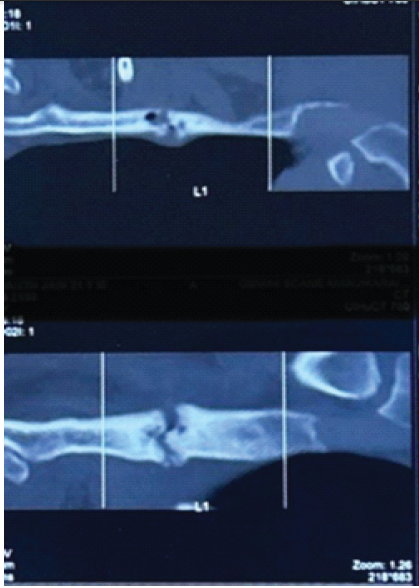

Computed tomography (CT) chest revealed cortical discontinuity of the lateral first rib with mixed lytic–sclerotic changes, subtle periosteal reaction, and mild soft-tissue inflammation. The lesion was seen indenting the divisions of the left brachial plexus and closely abutting the left subclavian artery (Fig. 1 and 2).

Figure 1: Computed tomography film showing fractured first rib with mixed lytic and sclerotic changes and periosteal reaction.